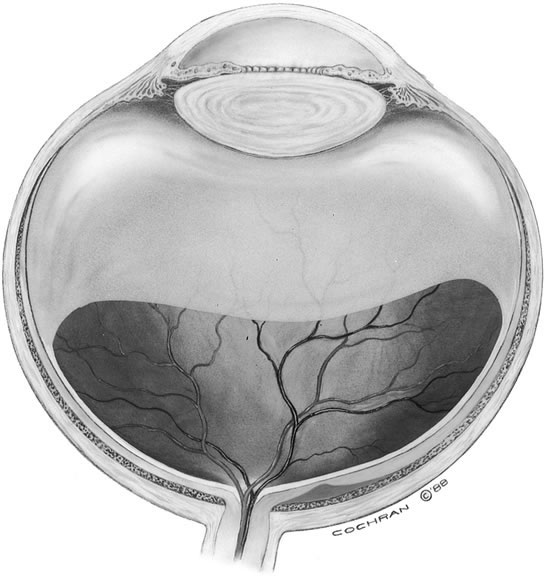

Stage 4

Posterior vitreous separation from the optic disc and macula, as evidenced by a peripapillary vitreous condensation ring on the posterior vitreous cortex (posterior hyaloid), occurs in a minority (30%) of macular holes and is termed stage 4. Earlier studies described PVD in up to 100% of eyes with macular holes. This is likely due to the difficulty in identifying a posterior vitreous separation. Posterior areas of vitreous liquefaction may appear to represent posterior vitreous separation, but the vitreous cortex remains attached (Fig. 19). A peripapillary ring is the only reliable sign of a complete posterior vitreous separation. Sophisticated ultrasound examination of the vitreous and laser biomicroscopy in conjunction with OCT may also be helpful in establishing the presence of a vitreous separation.87,92,93

Fig. 19. Vitreous cavity liquefaction with posterior hyaloid attached. (Margherio RR, Trese MT, Margherio AR et al: Surgical management of vitreomacular syndromes. Ophthalmology 1989;96:1441)